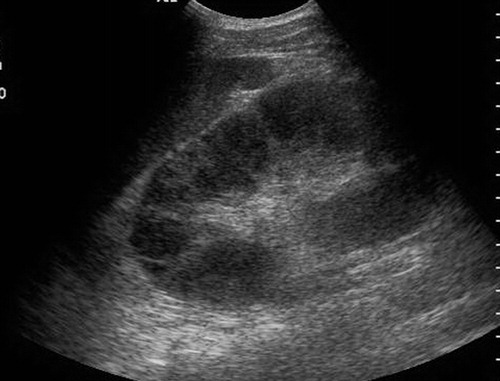

ARPKD

Autosomal Recessive Polycystic Kidney Disease (ARPKD) Typically presents around birth, though it can present later in childhood. Cases that develop later have a propensity to be associated with hepatic fibrosis. ARPKD is transmitted in an autosomal recessive pattern meaning two copies of an abnormal gene must be present in order for the disease or trait to develop.

- Infantile

- Kidney enlargement (sometimes massive)

- >80% liver cysts

- Multiple organs affected

- Hyperechoic